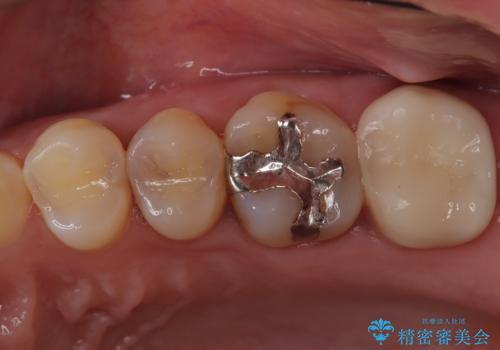

【セラミックインレー】虫歯の治療

- 定期検診にて虫歯を認めたため、セラミックインレーにて治療を行いました。

治療時にはラバーダムを装着しております。